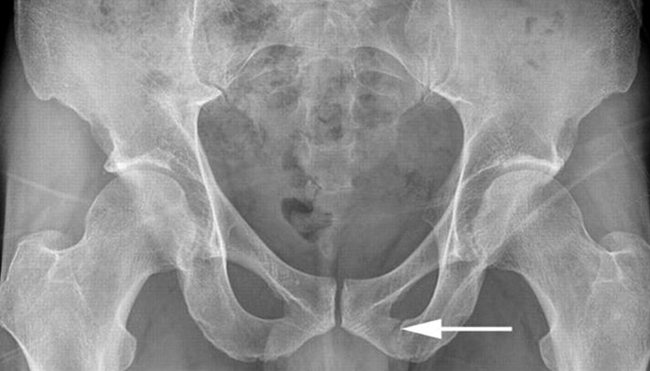

Наиболее информативным диагностическим методом является обзорная рентгенография костей таза. Переломы лобковых костей нередко сопровождаются повреждением внутренних органов с развитием серьёзных осложнений.

- рентгенография (обзорный снимок, фото лобковой кости);

Рентген

Наиболее информативным способом диагностики рассматриваемой травмы является рентгенография. Объемное изображение позволяет определить степень поражения костных элементов. Параллельно с традиционным рентгеном проводят прицельную рентгенографию, которая помогает определить, имеются ли у пациента смещения костных элементов.

Но самое информативное и достоверное обследование – рентгенограмма, которая может быть как обзорной, так и прицельной.